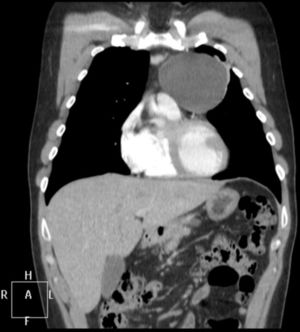

Se diagnosticó MG, confirmándose la presencia de niveles de anticuerpos antirreceptor de acetilcolina (AC anti-R Ach) de 22,1 nmol/L y un estudio de fibra aislada en músculo orbicular del ojo izquierdo, que mostraba potenciales con Jitter medio patológico y un 47% de bloqueos, compatible con alteración de la transmisión neuromuscular a nivel postsináptico. En la tomografía computarizada (TC) mediastínica se encontró una lesión quística en espacio prevascular de 78×79×77mm, de contornos bien definidos, pared fina, densidad líquido, sin captación de contraste y sin evidencia de ganglios patológicos (fig. 1).